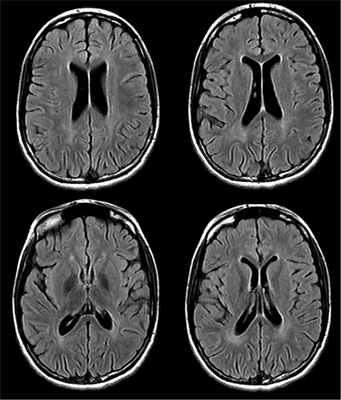

На МРТ головного мозга, выполненной в возрасте 11 лет, выявляется диффузная церебральная атрофия, задержка миелинизации перивентрикулярного белого вещества задних отделов больших полушарий, отмечается отрицательная динамика по сравнению с предыдущими исследованиями (рис. 4). Рис. 4. МРТ головного мозга от 30.09.16.

- Томографические методы. На КТ или МРТ головного мозга визуализируется атрофия коры больших полушарий и мозжечка, истончение мозолистого тела, умеренное расширение желудочков.